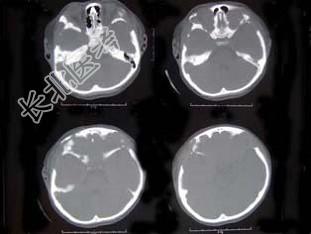

- 单项选择题女,22岁。反复头痛伴双下肢水肿10余年, 有多饮、多尿,近1个月来咳嗽, 呈阵发性,有时伴有脓痰, 低热,头部可触及柔软的软组织肿块及边缘不规则的骨缺损, 四肢及躯干皮肤可见散在出血点,双下肢凹陷性水肿, 结合所提供的图像,最可能的诊断是 ( )

A、韩-雪病

B、非骨化性纤维瘤

C、骨巨细胞瘤

D、骨纤维结构不良

E、内生软骨瘤